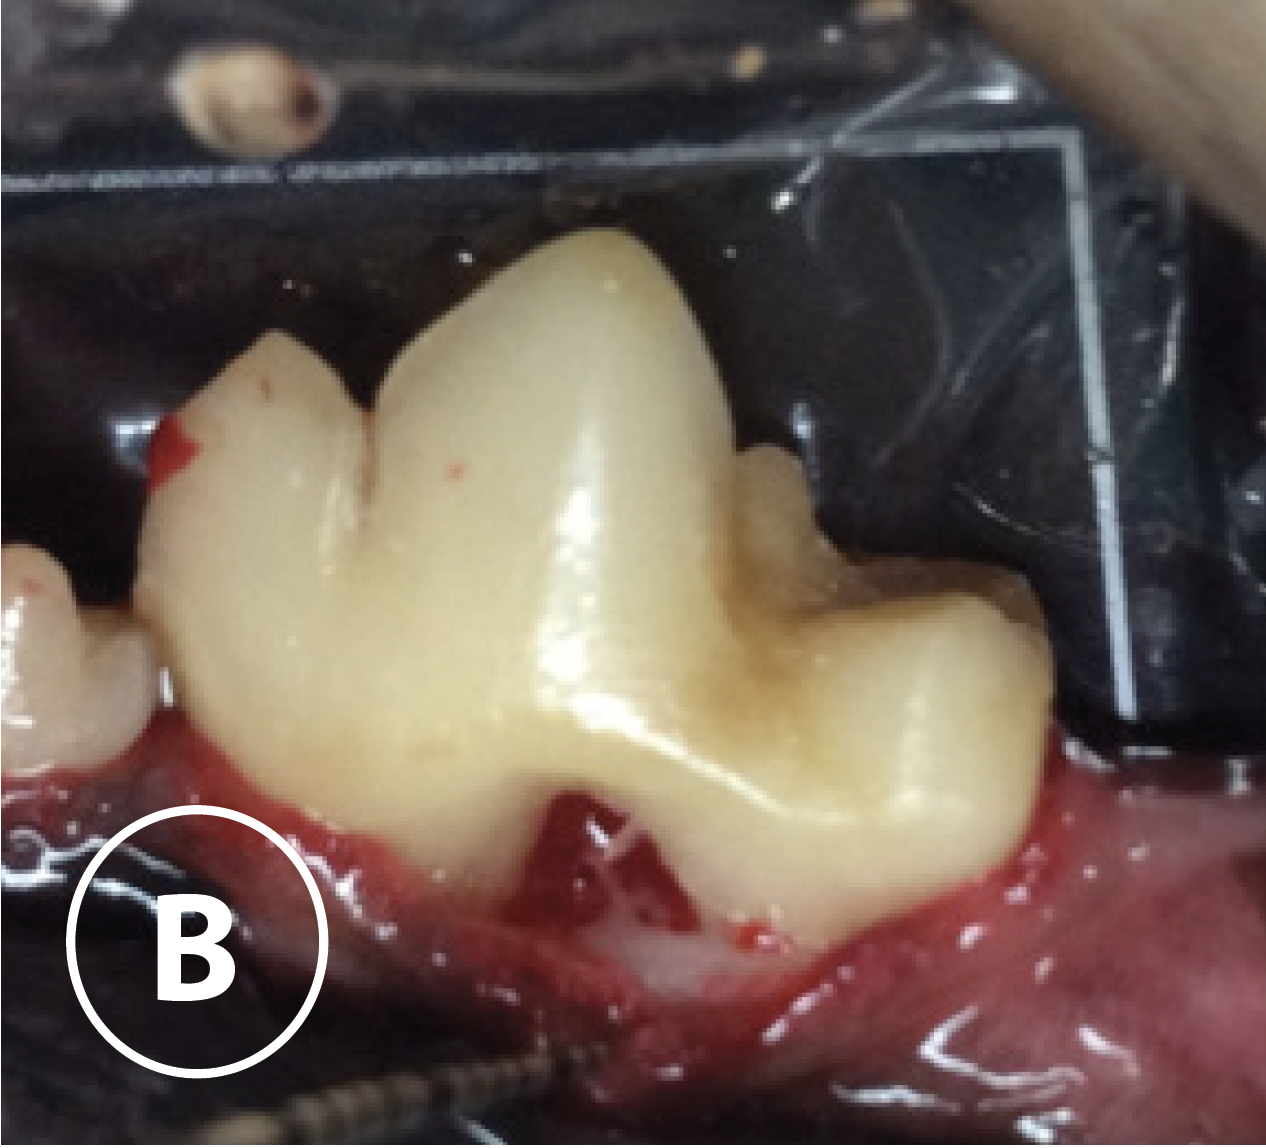

Envelope flap & root plane

B: Photograph 309 after envelope flap and root planning was completed. Note: furcation exposure and radiograph sensor placed lingually.

Envelope flap & root plane

B: Photograph 309 after envelope flap and root planning was completed. Note: furcation exposure and radiograph sensor placed lingually.